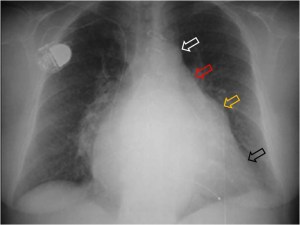

SIGNO DE LA SONDA NASOGÁSTRICA DESPLAZADA

El desplazamiento de la sonda nasogástrica a la derecha (que indica desplazamiento esofágico) en la radiografía de tórax, se ha descrito como el signo más fiable de rotura de la aorta torácica e indica la necesidad de realizar angioTC urgente. La primera imagen muestra el desplazamiento de la sonda (flechas verdes) así como un gran derrame pleural izquierdo (flechas naranjas).